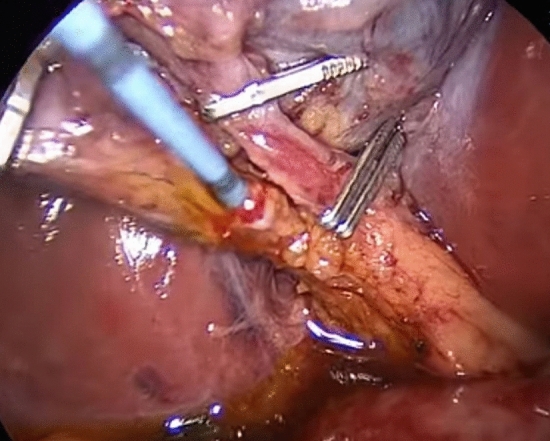

According to usual procedure, a laparoscopic cholecystectomy was performed with the standard four trocars technique. To avoid intestinal distension with air during ERCP, LC was started first. The cystic artery was located, clipped, and cut after the Calot’s triangle was dissected. The cystic duct was clipped high toward the GB, and a tiny incision was made near the clip for introduction of the cholangio-catheter to confirm the presence of CBD stones. A cholangio-catheter (4 Fr. Ureteric catheter) was used to catheterize the cystic duct (Fig. 2), and IOC was obtained following injection of 10 cc of diluted urografin utilizing a C-arm X-ray. The decision to perform IO-ERCP was made when the IOC revealed the presence of a CBDS or when the anatomy of the CBD was suspicious for the presence of a CBDS. A 0.035-inch guidewire was inserted into the cystic duct and progressed down past the sphincter of Oddi and into the duodenum by the surgeon. The duodenoscope was placed by the surgeon with the patient remaining in the supine position and advanced to the second portion of the duodenum, where the guidewire was encountered upon detection of the papilla (rendezvous technique) and was used to guide cannulation of the CBD using a sphincterotome. Endoscopic retrograde cholangiography (ERCP) was performed using diluted urografin given through the sphincterotome. A sphincterotomy was performed when a CBDS was discovered. The CBDS was subsequently removed using a retrieval Fogarty balloon (8.5 or 11.5 mm) (Fig. 3). After that, a completion cholangiography was performed to ensure that the CBD was free of stones. Care was taken to remove all gas from the stomach at the end of each ERCP to make the LC easier to complete.